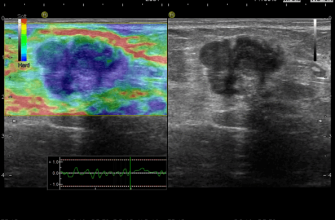

Компьютерная томография

Компьютерная томография (КТ) даёт более детальное изображение легких и может выявить заболевания‚ которые не были обнаружены на рентгенограмме. Это обследование особенно важно для людей с высоким риском рака легких.